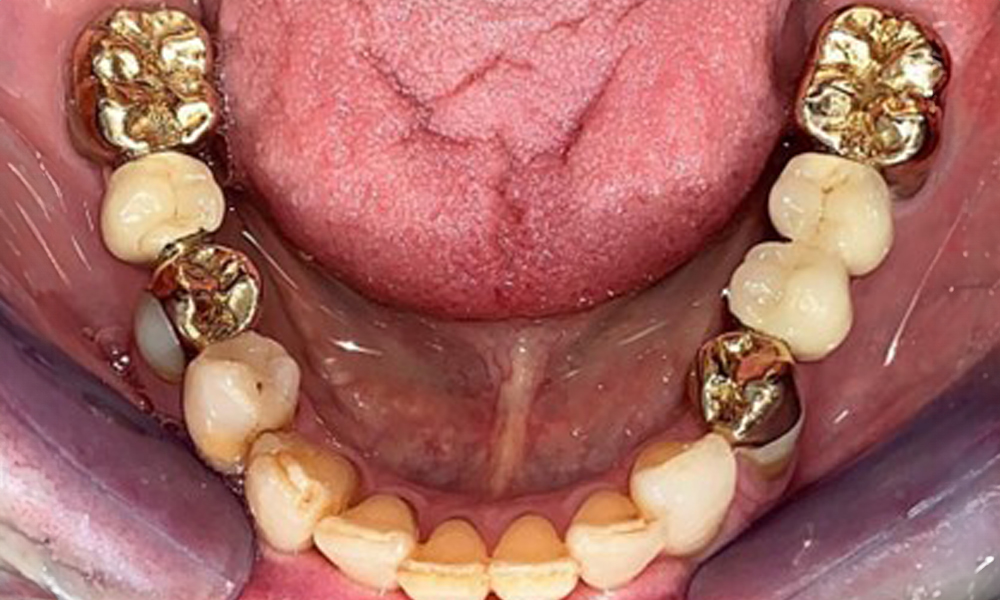

Оклузален изглед на долната челюст.

Фиг. 4: Оклузален изглед на долната челюст.

На пациентката е поставена комбинирана подвижна горночелюстна телескопична протеза преди повече от 25 години (фиг. 1, фиг. 2, фиг. 3) и тя е много доволна от протезите си. Пациентката има адекватна фиксирана протеза за долната челюст (фиг. 4).

Денталните открития са следните: Комбинирани снемаеми протези на импланти и телескопични протези, поддържани от зъби, на импланти 15, 13, 21, 23, 24, 25 и зъб 11 (фиг. 1, фиг. 2, фиг. 3). Пациентът е снабден с фиксирана долночелюстна протеза. Над зъби 37-34 и 45-47 бяха налични адекватни мостове (фиг. 4), краищата на коронките бяха интактни и нямаше активен кариес. Върху зъб 43 имаше композитна пломба с маргинална празнина. Имаше рецесия на долната гингива, която разкриваше от 1 до 3 mm от кореновата повърхност. Това се отнася и за 11.